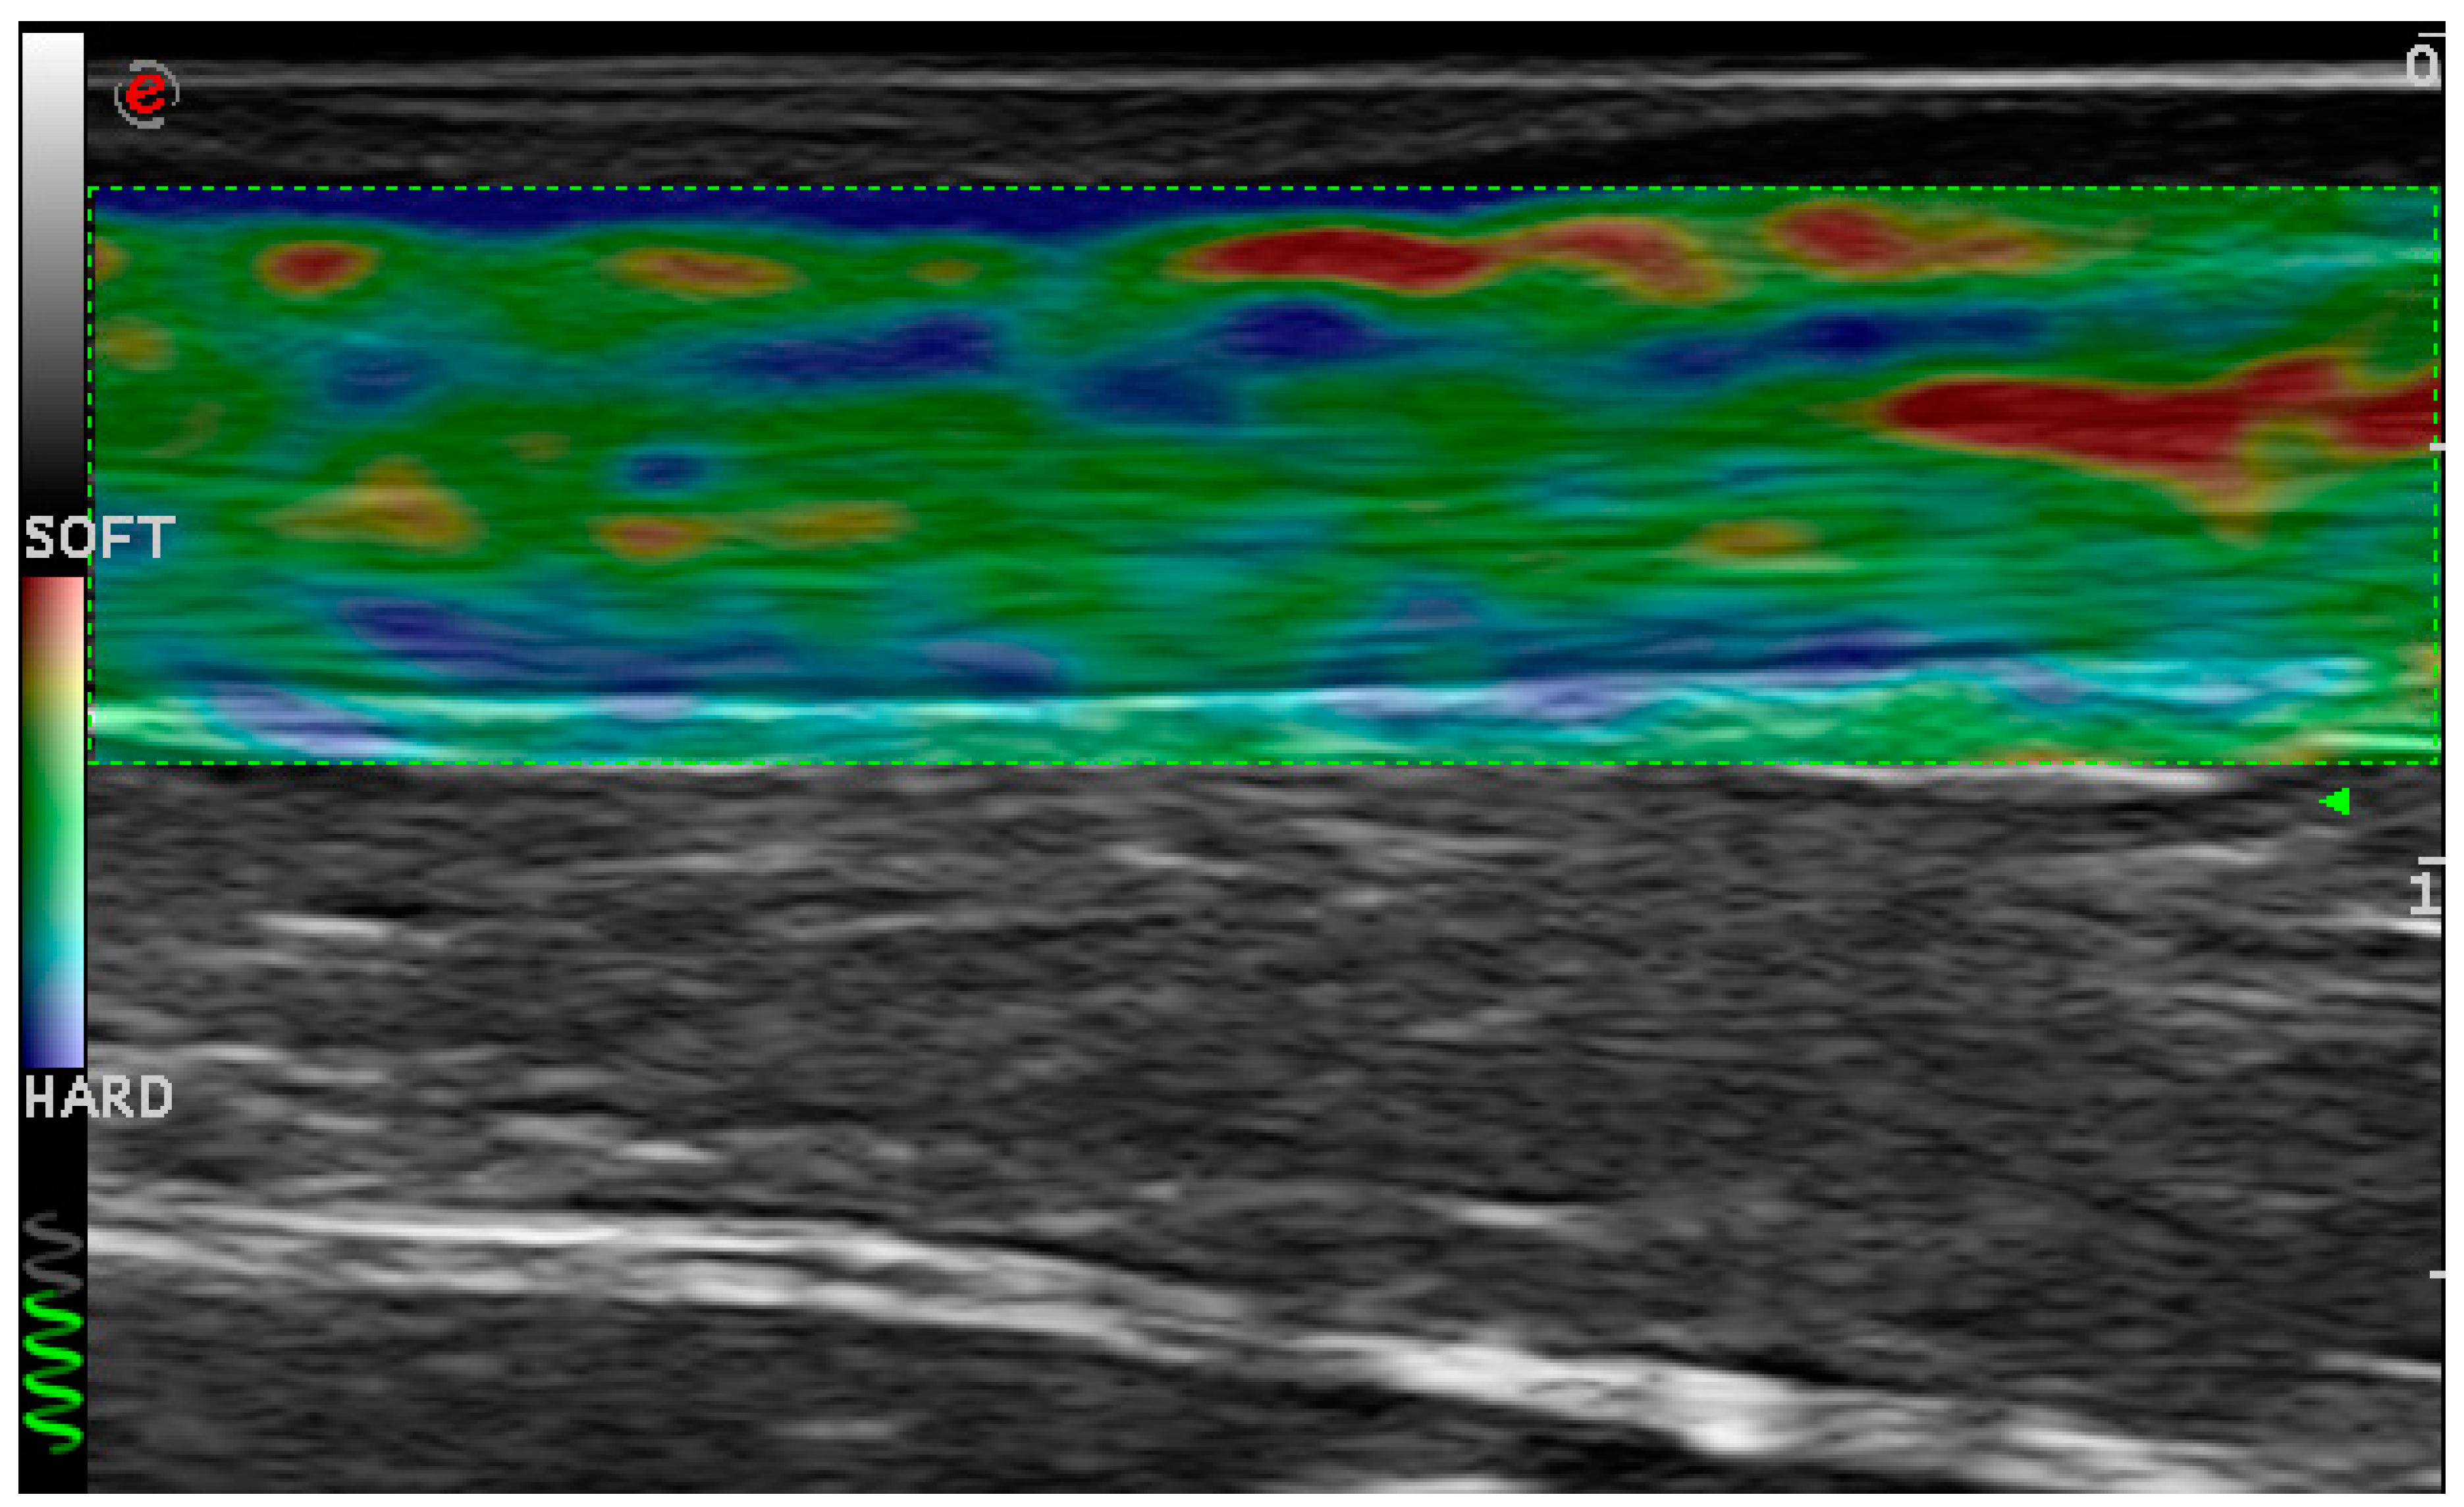

4.1.1. Ultrasonographic Evaluation